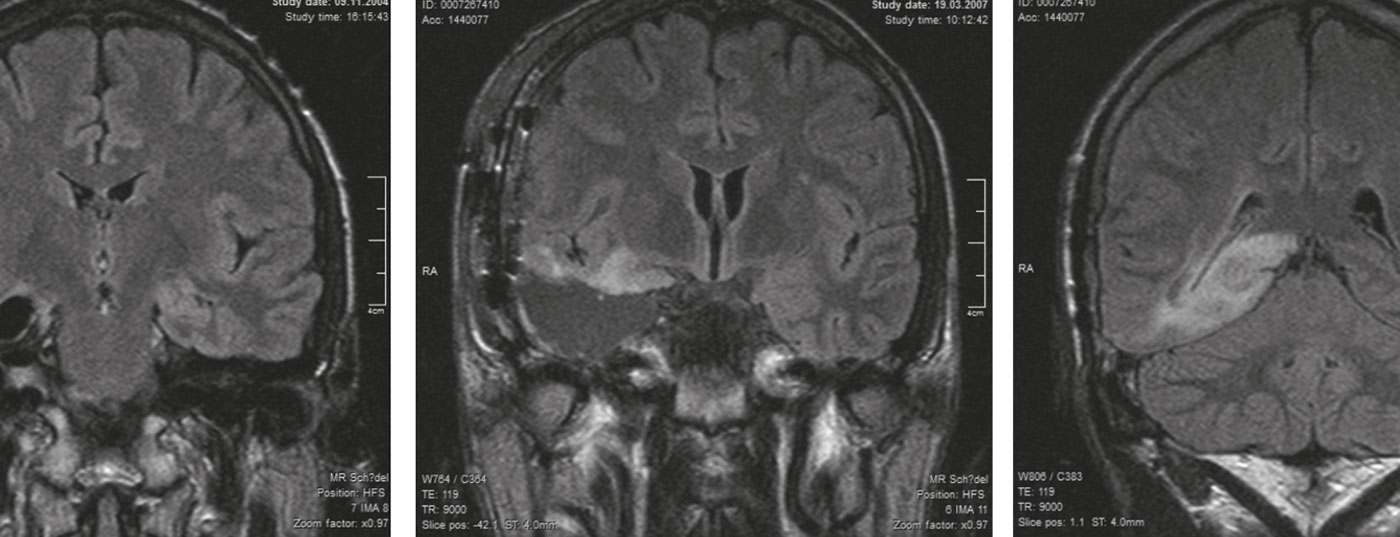

Warum niedrigmaligne Gliome gegenwärtig nicht heilbar sind

Grad II-Gliome werden in ihrer Bösartigkeit in der Frühphase eher unterschätzt. Für die Behandlung gibt es keinen Standard. Neben Abwarten wird immer häufiger eine aggressive chirurgische Taktik gewählt. Es kann aber auch damit keine Heilung erzielt werden.